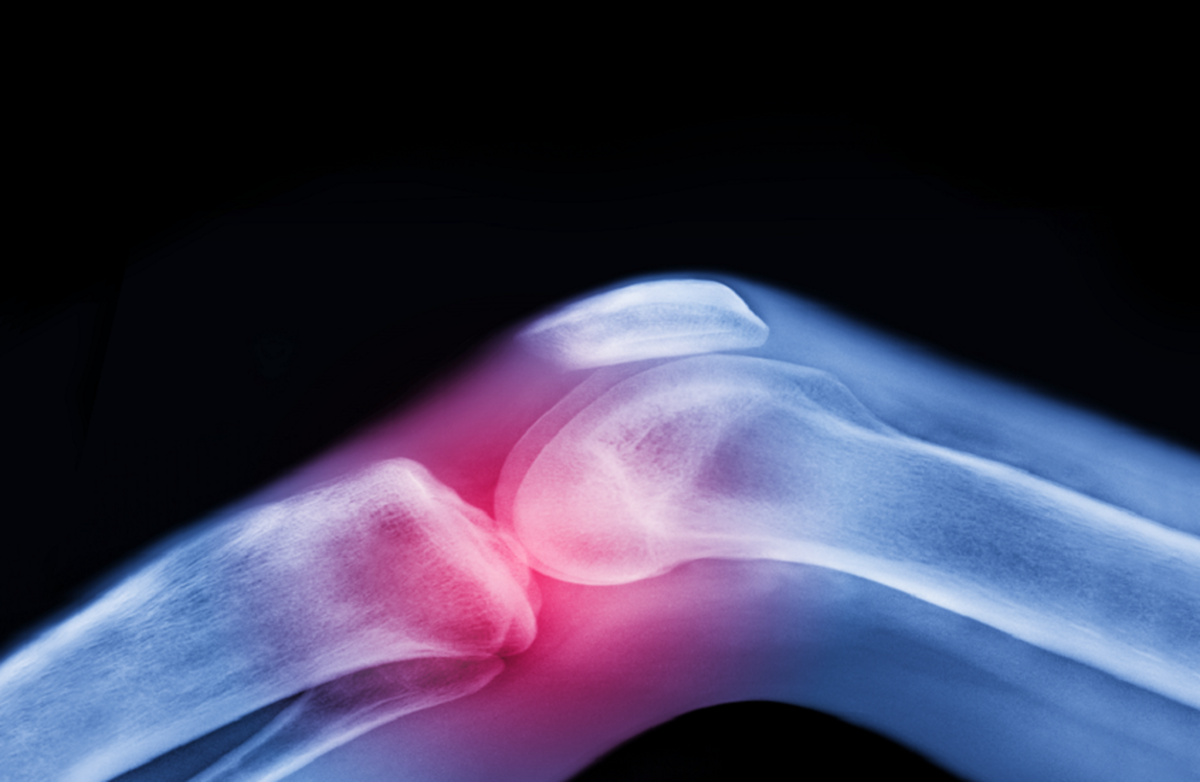

آرتروز فقط یک ساییدگی و پارگی مکانیکی مفصل نیست؛ بلکه بیماریای است که بر تمام اجزای آن تأثیر میگذارد: مایع سینوویال، غضروف، استخوان، رباطها، عضلات اطراف و حتی اعصابی که از حرکت پشتیبانی میکنند. حرکت منظم همه این اجزا را هدف قرار میدهد و سلامت مفصل را به طور مؤثر حفظ میکند.

غضروف، یک لایه محافظ که انتهای استخوانها را میپوشاند، فاقد منبع خون مستقیم است و برای سالم ماندن به حرکت متکی است. غضروف مانند اسفنج عمل میکند: هنگام حرکت فشرده میشود، مایع را آزاد میکند و مواد مغذی را دوباره جذب میکند و مفصل را انعطافپذیر و سالم نگه میدارد.

بنابراین، این تصور سنتی که آرتروز صرفاً یک «ساییدگی و پارگی» است، نادرست است. بلکه، آرتروز یک فرآیند طولانی فرسایش و پارگی است که در آن حرکت و ورزش منظم نقش کلیدی در حفظ سلامت مفصل ایفا میکند.